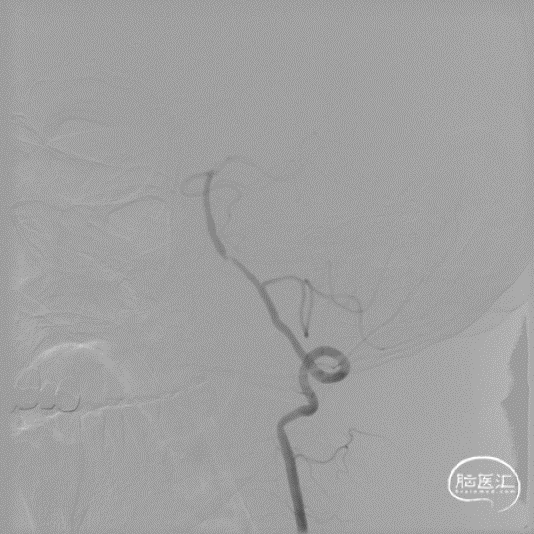

微导丝辅助微导管通过闭塞段,以赛诺神畅Neuro LPS-1.5-15mm球囊分次扩张闭塞段。

球扩后造影见闭塞段恢复正向血流M1段远端夹层表现。

沿微导丝输送赛诺神畅 NOVA颅内药物球扩支架2.25*20mm支架到位,支架输送顺利,全过程无明显张力变化。

6atm缓慢扩张释放支架。

释放支架后造影见支架中段稍有残留狭窄,以8atm缓慢再扩张,残留狭窄消失。